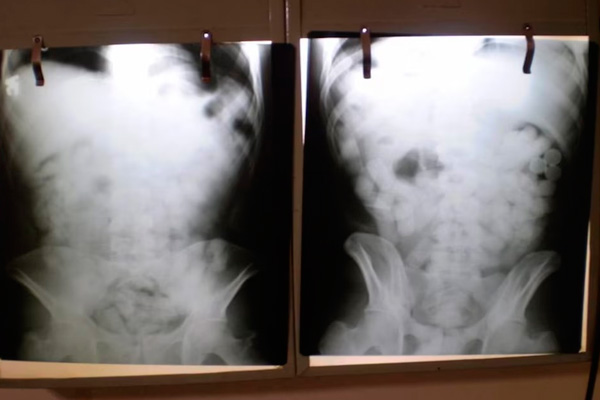

Una tomografía reveló la presencia de múltiples cuerpos extraños en la zona abdominal. Morales fue trasladado de inmediato al Hospital de Ezeiza bajo custodia policial, donde permaneció internado hasta el 28 de mayo. En ese lapso, evacuó las 90 cápsulas, que contenían en total 698 gramos de clorhidrato de cocaína.